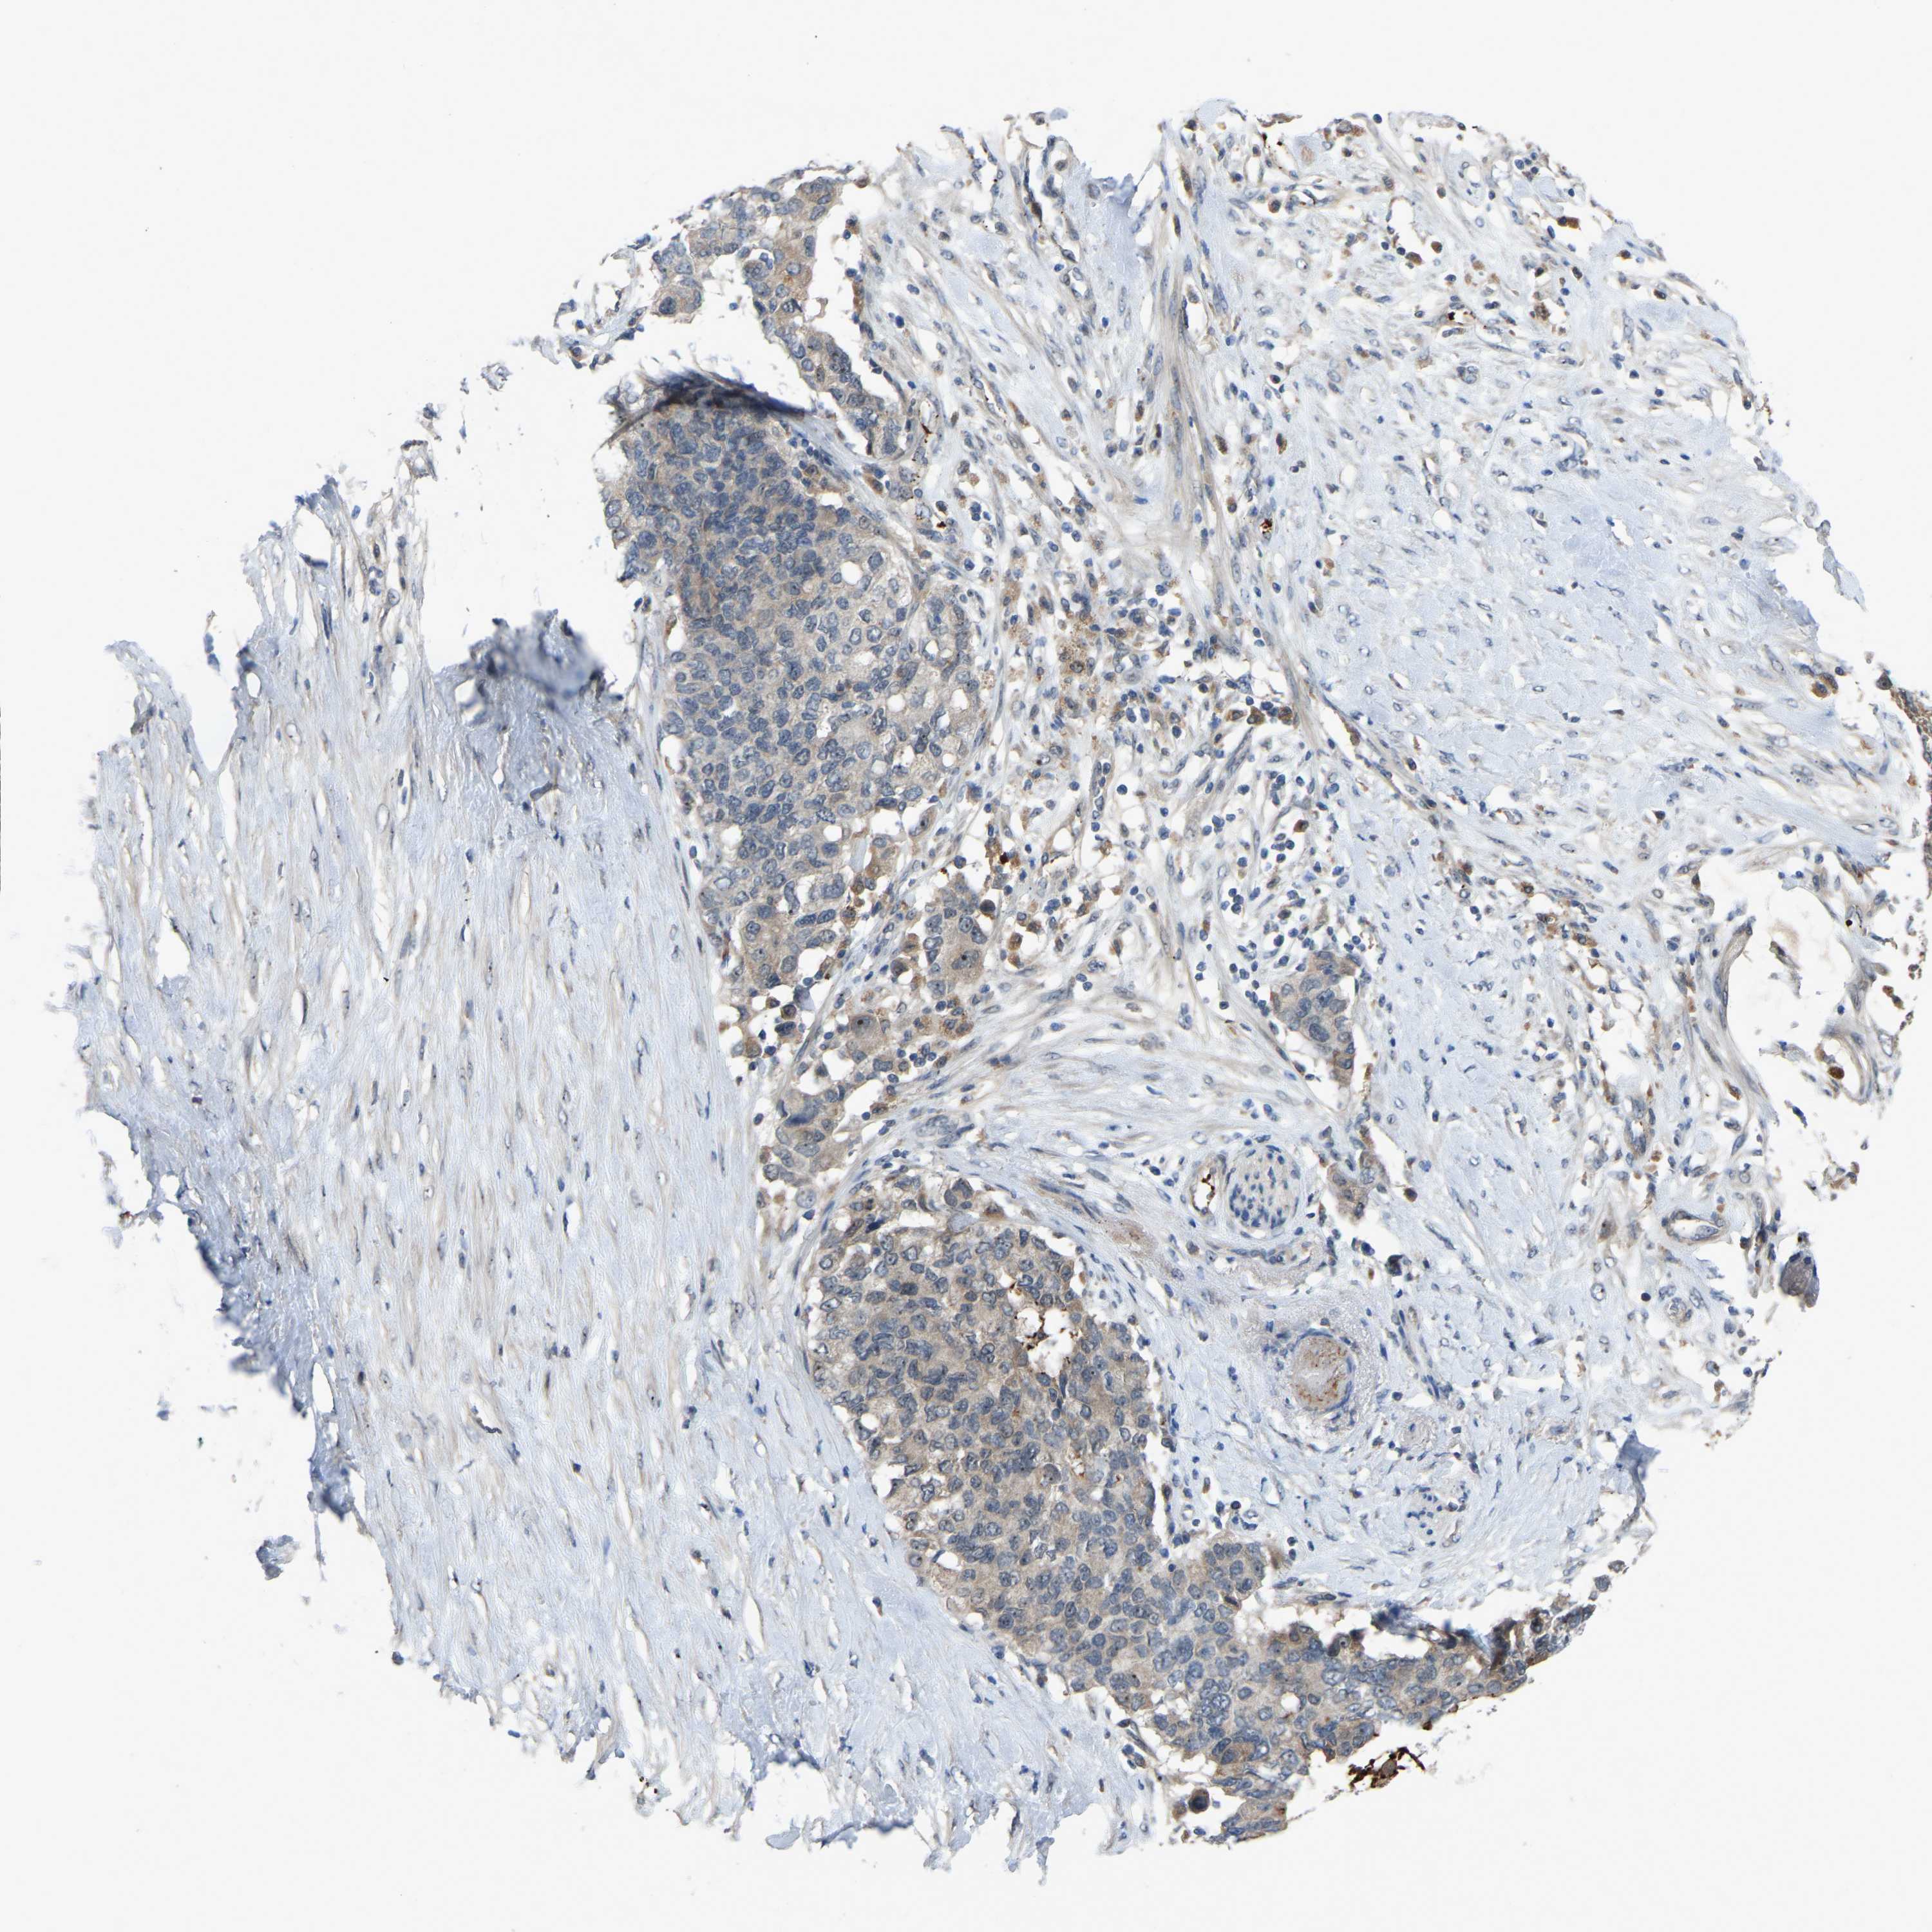

PANCREATIC CANCER - Protein expressioni

A mouse-over function shows sample information and annotation data. Click on an image to view it in a full screen mode. Samples can be filtered based on level of antibody staining by selecting one or several of the following categories: high, medium, low and not detected. The assay and annotation is described here.

Note that samples used for immunohistochemistry by the Human Protein Atlas do not correspond to samples in the TCGA dataset.

Antibody stainingi

Antibody staining in the annotated cell types in the current human tissue is reported as not detected, low, medium, or high, based on conventional immunohistochemistry profiling in selected tissues. This score is based on the combination of the staining intensity and fraction of stained cells.

Each image is clickable and will lead to virtual microscopy that enables deeper exploration of all samples and also displays staining intensity scores, fraction scores and subcellular localization as well as patient and tissue information for each sample.

Antibody HPA018840

Antibody HPA018909

Antibody CAB002684

Staining

High

Medium

Low

Not detected

Intensity

Strong

Moderate

Weak

Negative

Quantity

>75%

75%-25%

<25%

None

Location

Nuclear

Cytoplasmic/membranous

Cytoplasmic/membranous,nuclear

Adenocarcinoma, NOS

Adenocarcinoma, metastatic, NOS